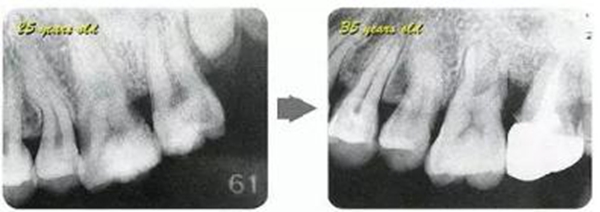

牙周病的發(fā)展因部位不同而發(fā)展程度不同的。10點(diǎn)后的狀態(tài)參考病例①和參考病例②的磨牙處的狀態(tài)相比較,思考下沒(méi)接受治療病情發(fā)展的特別性吧。

參考病例① 35歲女性

在左下第一磨牙在25歲時(shí)近中處可以看到垂直性的骨吸收,但35歲時(shí)吸收停止,原本沒(méi)有見(jiàn)到的遠(yuǎn)中處骨吸收的,現(xiàn)在卻吸收得很?chē)?yán)重。

在右下處,原本有大量骨吸收的第一磨牙處的吸收卻變緩慢,原本沒(méi)有吸收的第二前磨牙卻出現(xiàn)了吸收。出現(xiàn)吸收的左上第一磨牙的遠(yuǎn)中處,吸收得越來(lái)越多了。